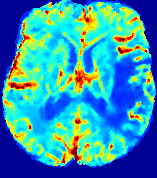

LesionRefer to captionRefer to captionRefer to captionRefer to captionRefer to captionRefer to caption𝐕rgbsubscript𝐕𝑟𝑔𝑏{\bf{V}}_{rgb}Refer to captionRefer to captionRefer to captionRefer to captionRefer to captionRefer to caption𝐕2subscriptnorm𝐕2{\|\bf{V}}\|_{2}Refer to captionRefer to captionRefer to captionRefer to captionRefer to captionRefer to captionRefer to caption3.53.53.52.82.82.82.12.12.11.41.41.40.70.70.70.00.00.0(mm/s)𝑚𝑚𝑠(mm/s)D𝐷DRefer to captionRefer to captionRefer to captionRefer to captionRefer to captionRefer to captionRefer to caption0.0200.0200.0200.0160.0160.0160.0120.0120.0120.0080.0080.0080.0040.0040.0040.0000.0000.000(mm2/s)𝑚superscript𝑚2𝑠(mm^{2}/s)Slice #1Slice #2Slice #3Slice #4Slice #5Slice #6

Figure 3: PIANO feature maps for one stroke patient, where the lesion is located in the left hemisphere. Top row: segmented stroke lesion region (white) on different slices, obtained from ISLES 2017. The corresponding slices for the PIANO feature maps are shown in the following rows.

For a better insight into an estimated velocity field 𝐕𝐕{\bf{V}} and diffusion field 𝐃𝐃{\bf{D}}, we compute the following maps: (1) 𝐕rgbsubscript𝐕𝑟𝑔𝑏{\bf{V}}_{rgb}: Color-coded orientation map of 𝐕=(Vx,Vy,Vz)T𝐕superscriptsuperscript𝑉𝑥superscript𝑉𝑦superscript𝑉𝑧𝑇{\bf{V}}=(V^{x},V^{y},V^{z})^{T}, obtained by normalizing 𝐕𝐕{\bf{V}} to unit length and mapping its 3 components to red, green, blue respectively; (2) 𝐕2subscriptnorm𝐕2\|{\bf{V}}\|_{2}: 222 norm of 𝐕𝐕{\bf{V}}; (3) D𝐷D: scalar field in Eq. 5.

Fig. 3 and Fig. 4 show the PIANO feature maps estimated from two ISLES 2017 patients: all are highly consistent with the lesion in both cases. Details of the blood flow trajectories are revealed in 𝐕rgbsubscript𝐕𝑟𝑔𝑏{\bf{V}}_{rgb} by the ridged patterns and the sharp changes of colors in the unaffected (right) hemisphere, while the flat patterns appearing within the lesion provide little directional information about the velocity and indicate low velocity magnitudes. Velocity magnitudes are more directly visualized via 𝐕2subscriptnorm𝐕2\|{\bf{V}}\|_{2}, from which one can easily locate the lesion where 𝐕2subscriptnorm𝐕2\|{\bf{V}}\|_{2} is low. D𝐷D also indicates lower diffusion values in the lesion, though with less contrast potentially due to the fact that it captures the accumulated effect of CA diffusion at the voxel-level.